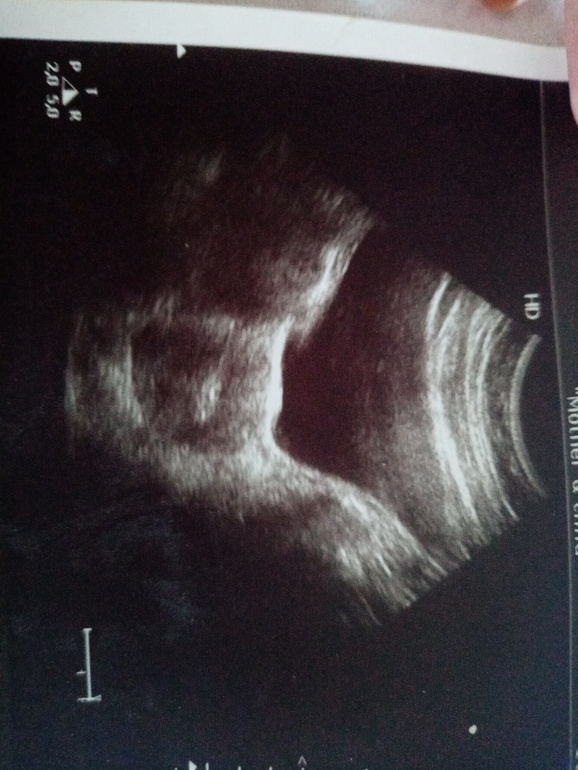

При переносе первых двух ембрионов было сделано фото Узд,где врач показали что успешно все ( два)они переместили.

Через день на второй перенос (одного ембриона) на УЗИ показало не три пятнышка,а только два.(с которого они показали что перенесли один) а один уже больше по размеру.

На фотокартке было зафиксировано всего два ембриона,которые до последнего росли

Ой нет) эти пятнышки на узи это капля эмбриологической среды с которой их переносят)))) сам эмбрион микроскопический и первые две недели увидеть его на узи нельзя

Если бы эмбрионы были бы видны на узи в таком микроскопическом размере... Вам все верно написали-это капельки среды или пузырьки воздуха. Но ваша версия, безусловно, красивее)))

На этом сроке не видны эмбрионы в матке)))) эти пятнышки-это метки воздухом, которые говорят о том, что эмбрион перенесен в полость матки и катетер пуст.

здесь хорошо видно